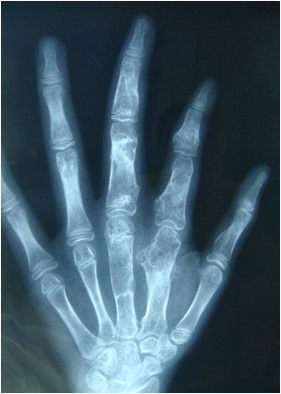

Ollier病-术前